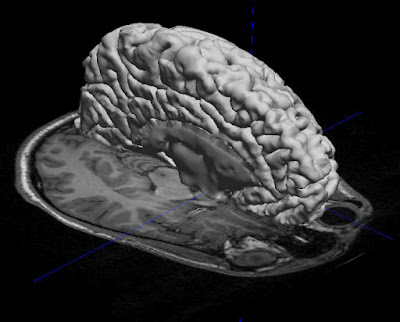

Eventually, when the lab technicians overlaid these images, they were able to create a 3D image of my entire brain, which might have looked something like this:

Pretty cool, huh?